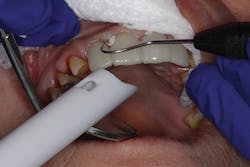

In the second case, a full arch of full-contour, anterior zirconia restorations are primed with zirconia primer and ready to be tried in (figure 6). Due to the patient's short clinical crowns, TheraCem was chosen to provide maximum retention of the zirconia restorations. In this case, attrition due to bruxism had reduced the height of the patient's teeth, and almost no vertical reduction was performed from first premolar to first premolar (figure 7). After try-in, the prostheses were rinsed and dried, and the front four crowns were delivered with TheraCem (figure 8). After preliminary cleanup of the cement, the upper left teeth were rinsed and gently dried (figure 9). The upper left restorations were then delivered with TheraCem (figure 10). This was followed up with another preliminary cleanup of the cement (figure 11). A retracted view shows the final restorations after a thorough cleanup (figure 12).

Figure 8: Delivery of front crowns